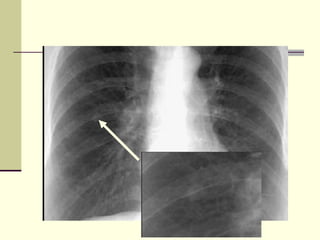

CONSOLIDATION Density in right upper lung field  Lobar density  Loss of ascending aorta silhouette  No shift of mediastinum  Transverse fissure not significantly shifted  Air bronchogram

CONSOLIDATION Density inright upper lung field Lobar density Loss of ascending aorta silhouette No shift of mediastinum Transverse fissure not significantly shifted Air bronchogram